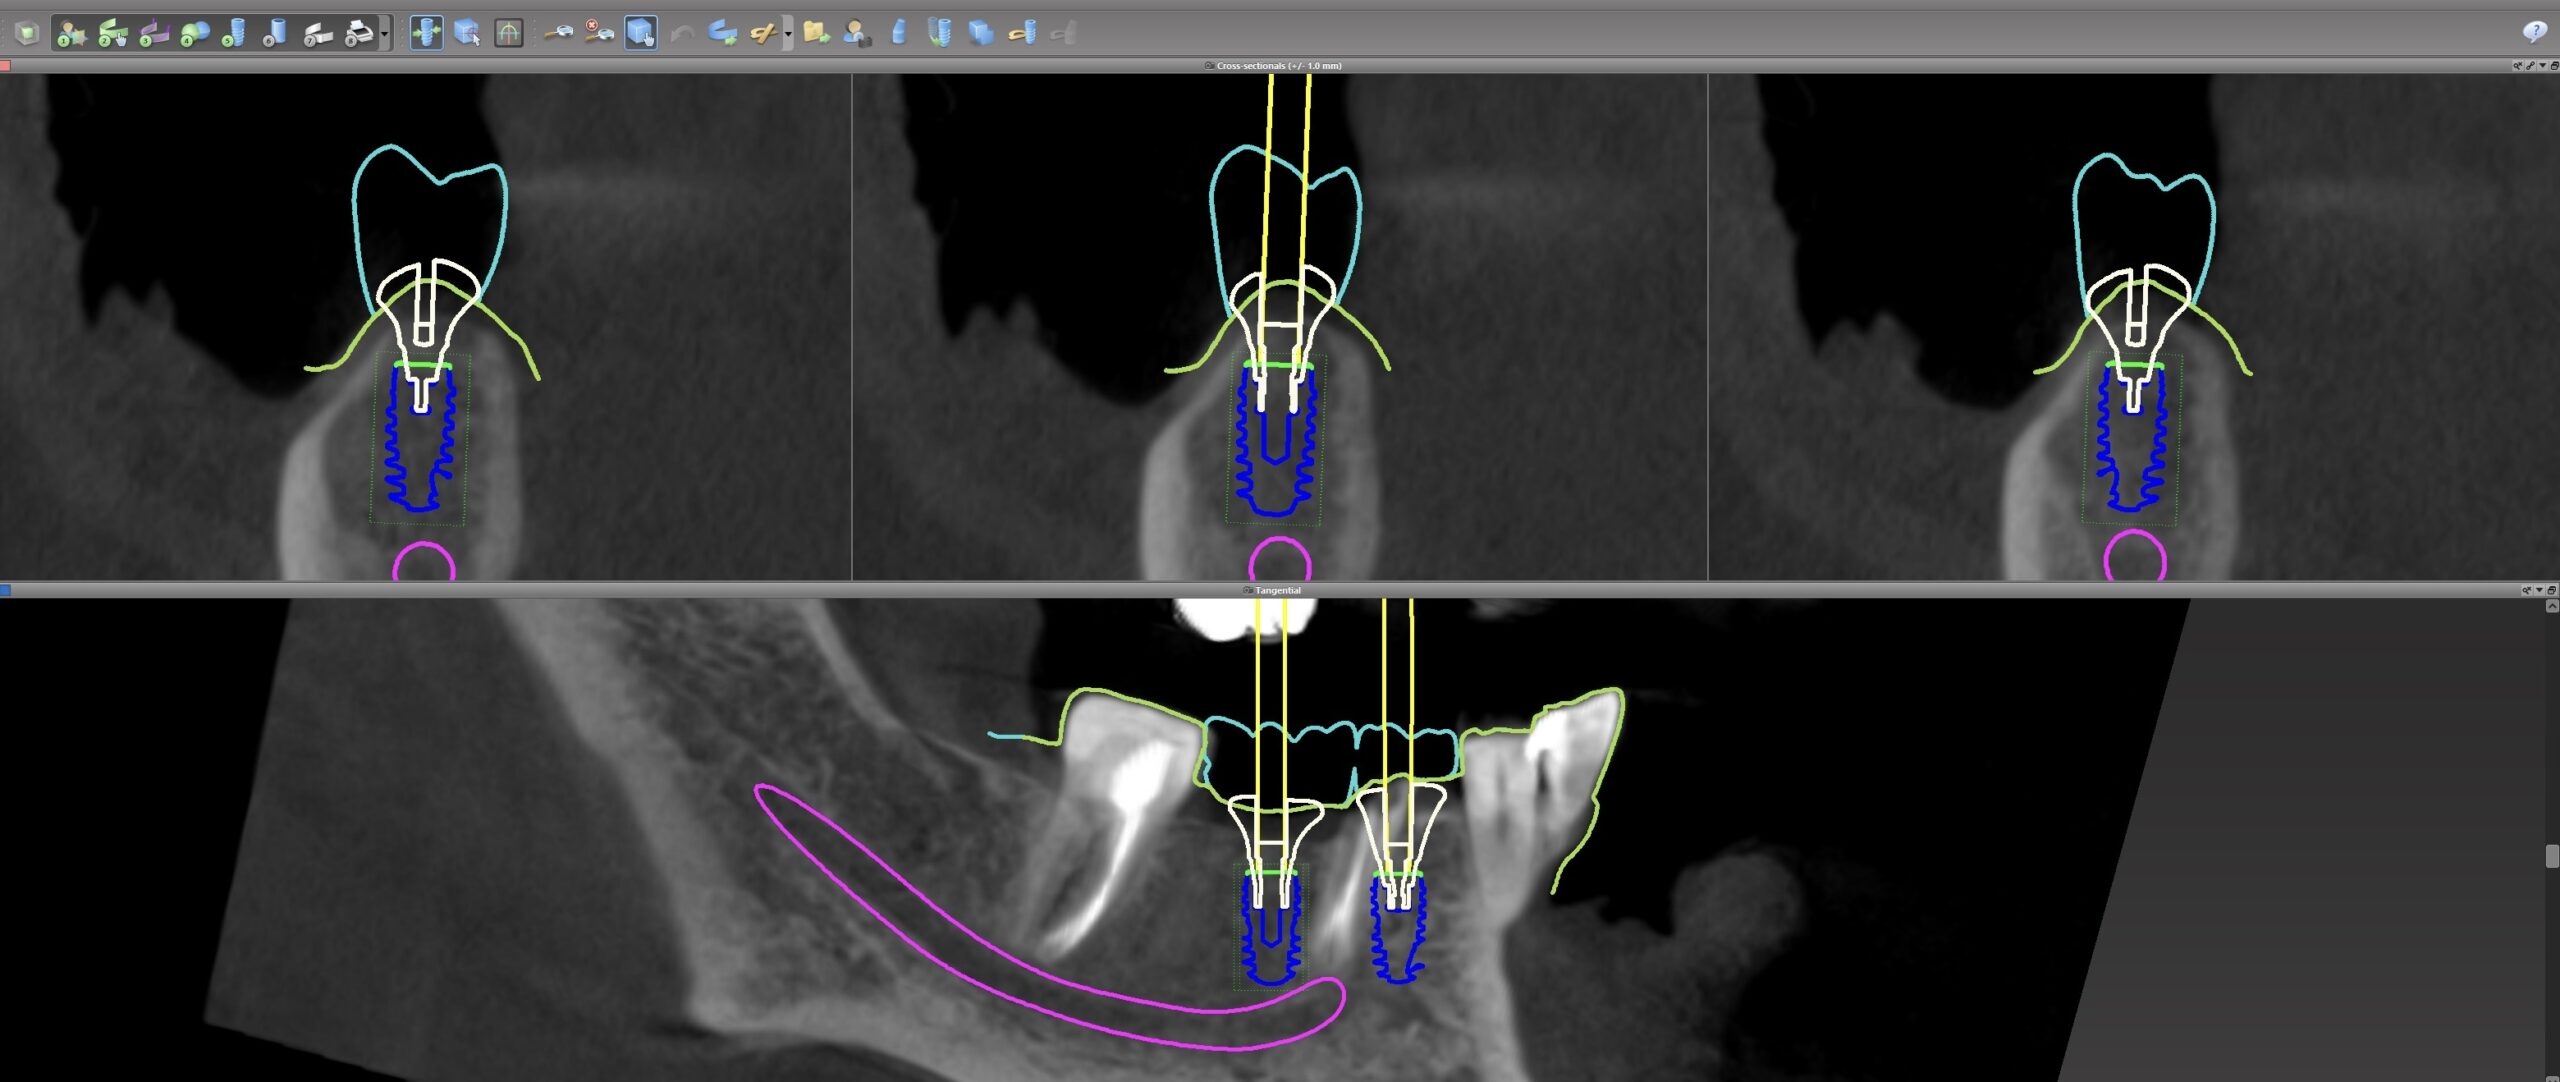

名古屋でインプラントを検討する際、最も重要なのは「神経との距離」です

特に下顎奥歯のインプラントでは、**下歯槽神経(かしそうしんけい)**という神経との位置関係が重要になります。

近年の臨床研究では、インプラントと神経管の距離によってリスクが大きく変化することが分かっています。

具体的には次の通りです。

・神経から2mm以上離れている場合:神経障害報告はほぼ0%

・1〜2mm:神経障害は非常に稀

・1mm未満:神経症状が急増する可能性

名古屋でも近年はCT診断を行う歯科医院が増えていますが、

CTを撮ること自体よりも重要なのは

CTデータをどのように読み取り治療設計に反映するかです。

・CTで神経管位置を確認

インプラント相談の際にCTを確認すると

「入れる位置が数ミリ変わるだけで安全性が大きく変わる」

というケースは珍しくありません。